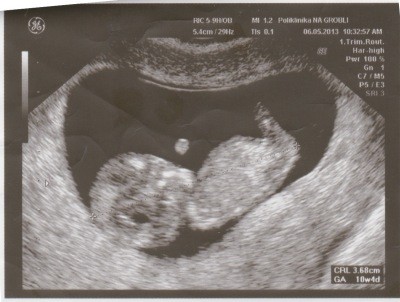

Laperedhil piękności nie mogę się napatrzeć. Ja idę w piątek, zostały dwa dni. I mam nadzieje, że również wam się pochwalę moja dzidzią, A za tydzień jeszcze raz ale idę na to genetyczne troszkę się boję, ale to chyba normalne.